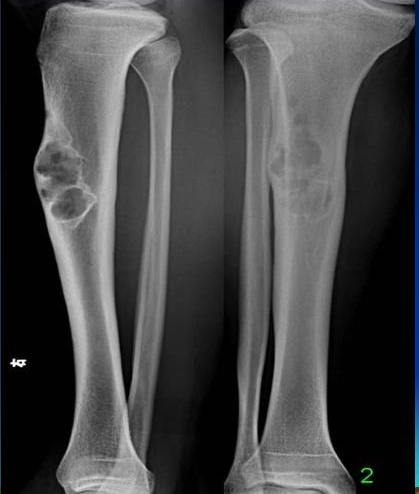

近日,手外•足踝•显微外科来了一位特殊病人,一个7岁小男孩,在玩轮滑时不小心扭伤脚踝,致使踝关节肿胀、压痛,拍片发现胫骨骨质异常,被告知可能是肿瘤,要求住院进一步确诊。家属一听是“肿瘤”,吓得赶紧给孩子办理了住院手续进一步治疗。

科室主任余化龙、副主任医师刘亚东积极组织管床医生及科室医生结合检查结果进行讨论,最终诊断为:非骨化性纤维瘤。

非骨化性纤维瘤(non-ossifying fibroma, NOF)是一种少见的纤维组织肿瘤。这种肿瘤过去曾被认为是瘤样病损,即干骺端纤维性骨皮质缺损,1942年Jaffe和Lichtenstein认为它是一种真性肿瘤,1958年Jaffe正式命名为非骨化性纤维瘤。目前多认为是良性纤维组织细胞性肿瘤。

非骨化性纤维瘤是来源于纤维组织的肿瘤,发病率不高,占肿瘤总数的0.81%,占良性肿瘤的1.45%,男女之比为1.38:1,好发于儿童和青少年,年龄多在11~20岁(29.6%),容易发病的人群主要集中在儿童以及青少年,容易发病的部位是下肢长管状骨,或者是胫骨、股骨以及腓骨。一般很少出现症状,有时在病理性骨折后才发现,主要表现为局部轻微疼痛、压痛、病理骨折,儿童、青少年出现膝踝或髋关节疼痛,该疾病发展缓慢,x射线检测可以发现。

该瘤可自行消退,对x线能明确诊断,而病灶又不超过患骨横径的1/2,不会发生病理性骨折者,可不急于手术,注意其自然愈合情况。

小型者无需治疗,较大而有症状者可行刮除植骨术,若病变很大,且位于次要骨端(如腓骨上端,尺骨下端),可采用整段切除术。

本瘤可自行消退,未引起病理性骨折,医生建议孩子可以出院回家观察。